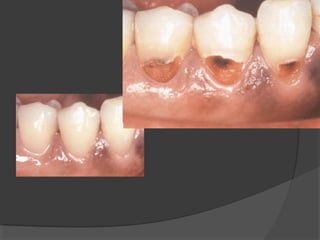

e) Class V Cavities:

Are smooth surface cavities occurring in the

gingival third of the buccal and lingual surfaces of

all teeth, excluding cavities occurring in anatomical

pits in the palatal surfaces of upper incisors, where

they are grouped with Class I cavity.